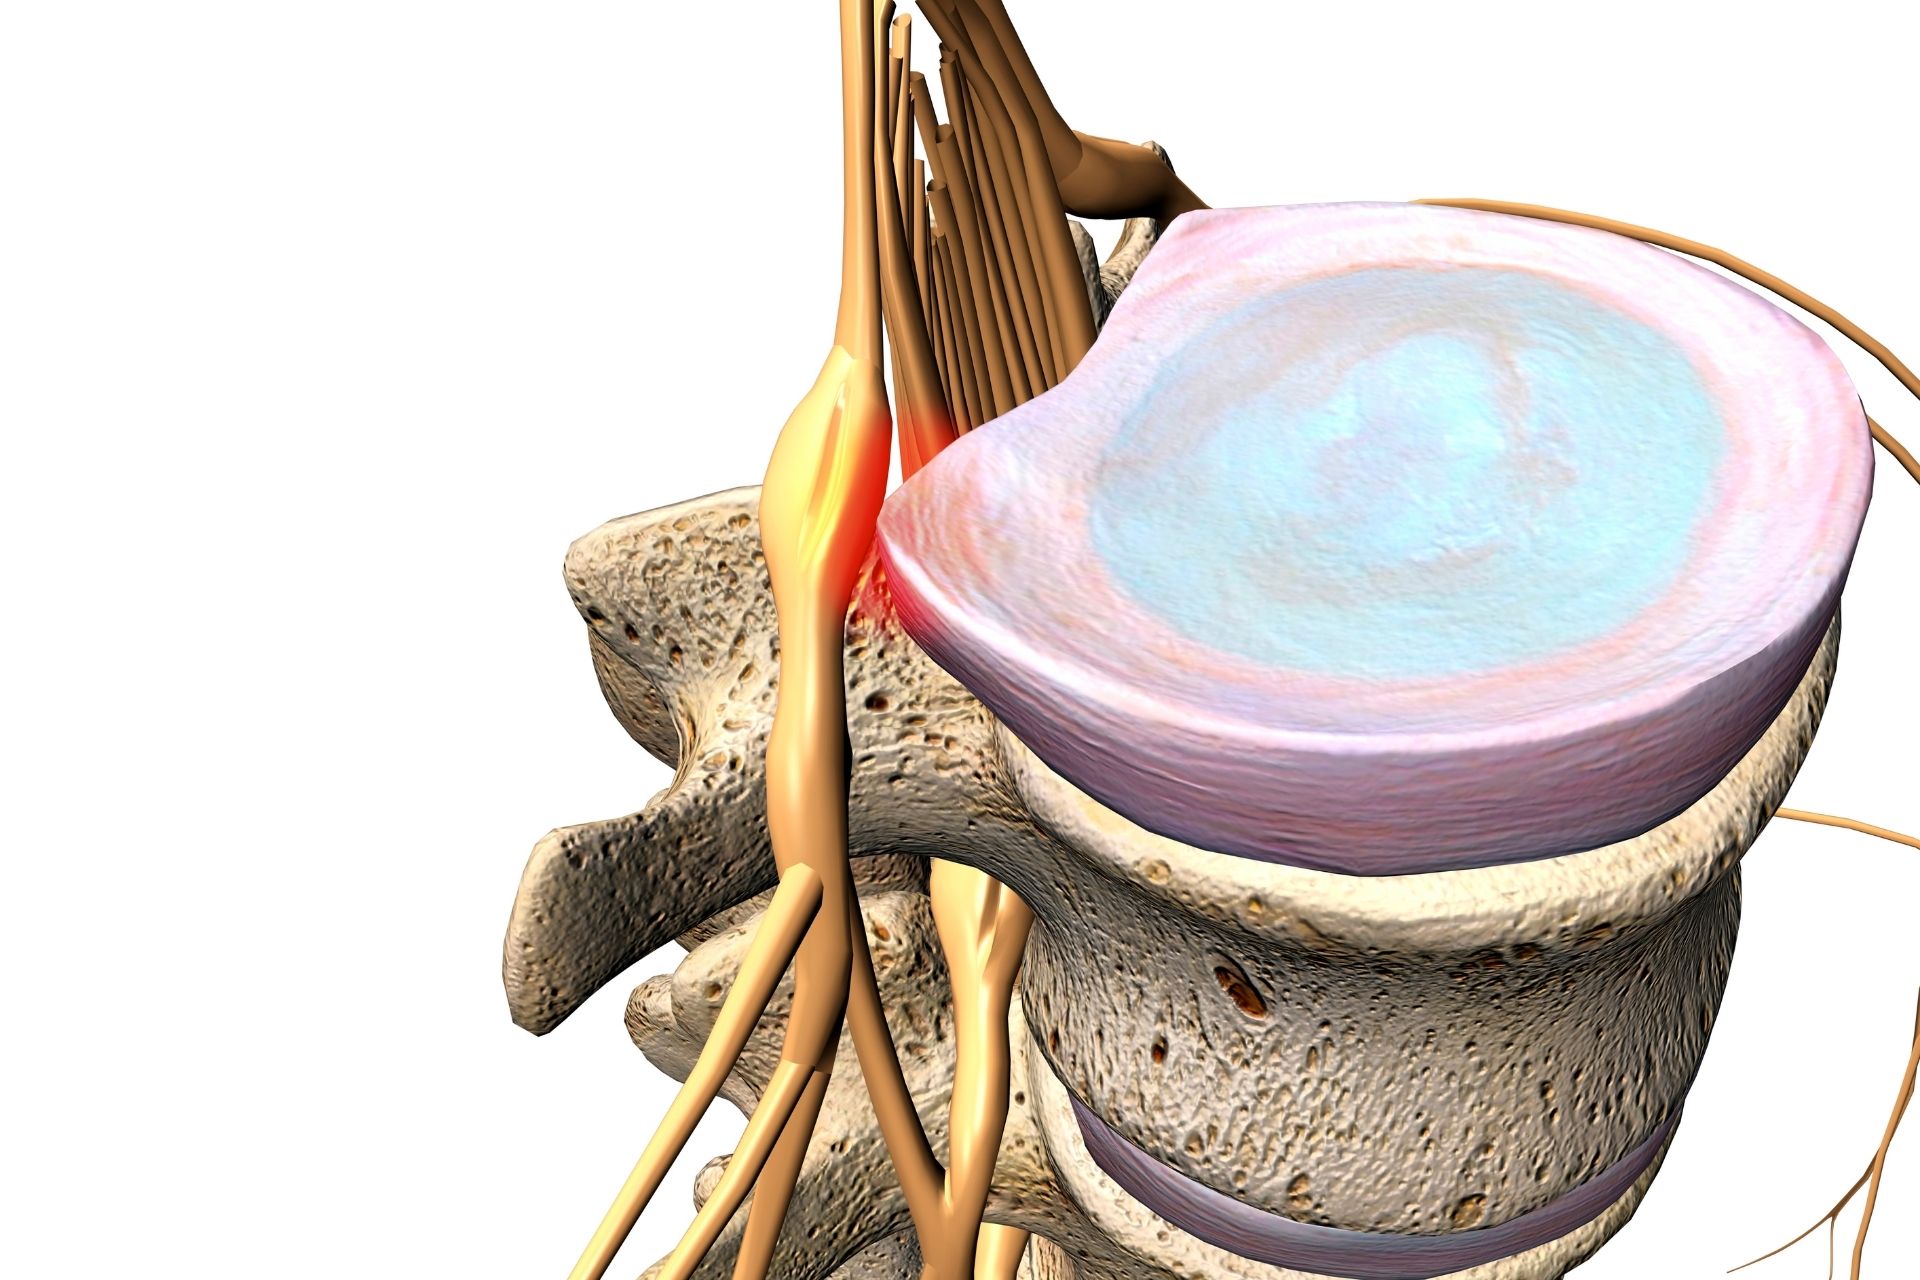

Spinal Disc Herniation Physical Therapy focuses on relieving pressure caused by herniated or bulging spinal discs. At Advanced Spinal Care, we use a combination of physical therapy techniques, spinal decompression, and chiropractic care to reduce inflammation, improve mobility, and help the disc heal naturally. The goal is to ease nerve compression and get you moving comfortably again—without invasive procedures.

Spinal Disc Herniation Physical Therapy is recommended if you’re experiencing back pain, numbness, tingling, or weakness due to a herniated disc. It’s especially effective for patients looking to avoid surgery or long-term medication. Whether your injury came from an accident, repetitive strain, or degeneration over time, treating it early can prevent it from getting worse.